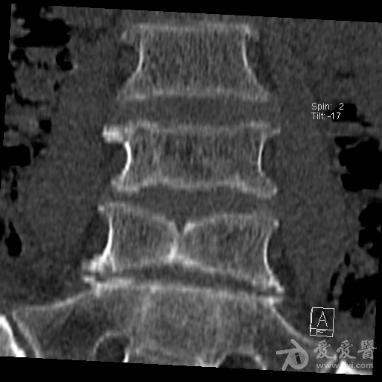

术前检查:同时存在t2蝴蝶椎及t3半椎体畸形.

图片尺寸352x490

术前三维ct重建术前检查:同时存在t2蝴蝶椎及t3半椎体畸形.

图片尺寸351x490